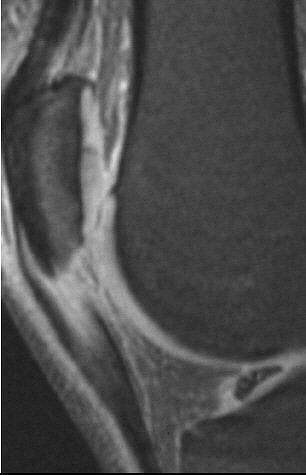

| Sagittal MR image of jumper's knee depicting an abnormal signal and the size of the patella tendon in a basketball player. Image courtesy of Duke University Medical Center, Durham, NC. |

That’s why Duke’s basketball players are imaged for jumper’s knee with MRI before and after the NCAA season. "With sports that have a lot of jumping and landing, tendons or ligaments can become degenerated over time," Major said. "Several players did indeed have changes that would be diagnostic of jumper’s knee. They don’t complain about the pain; they think they’re supposed to have some, so they’re soaking this or icing that, and that’s ‘expected’ when you’re playing at that level.